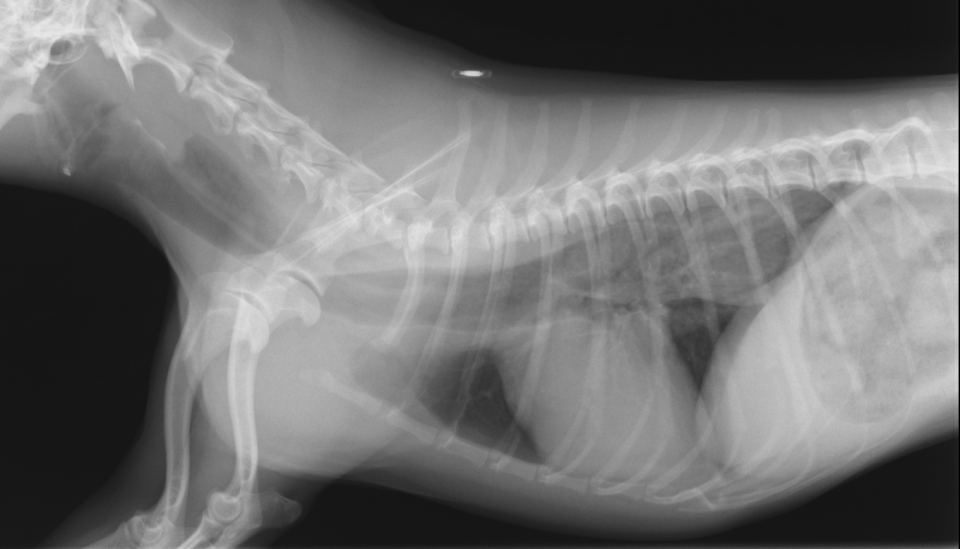

case.1気管支肺胞腺癌による呼吸器症状と胸水の貯留を呈した猫